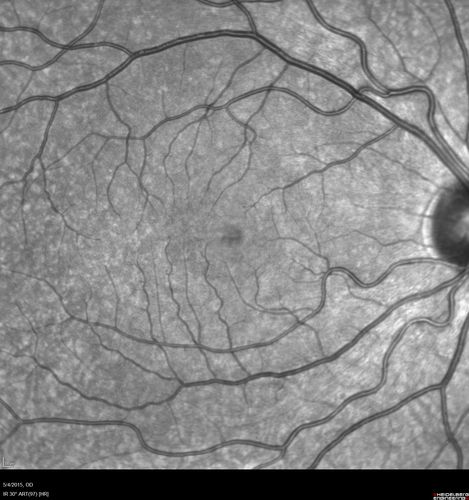

CRVO 25 year old man - Heterozygous Factor V Leiden

20/100 initial vision. Improved to 20/30 with Lucentis which continued for 3 years, treat and extend, and stopped.